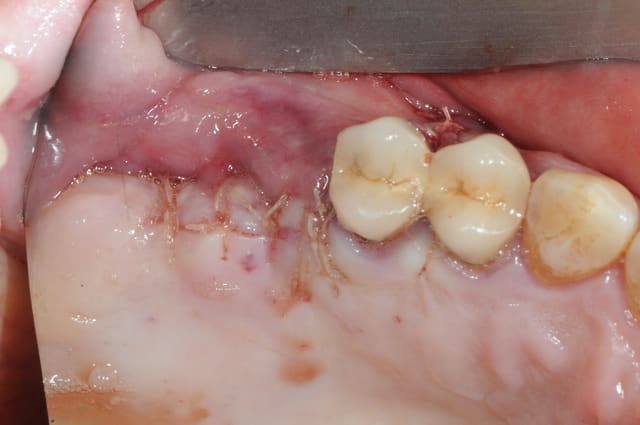

je dois pratiquer un rehaussement de plancher sinusien par volet latéral et je ne sais comment gérer le décollement de la membrane de Schneider au niveau de la communication bucco sinusale

Dès le départ, je m'inquiète au niveau du décollement du lambeau sur la CBS, on risque de déchirer à ce moment là

je joins quelques captures pour vous faire une idée